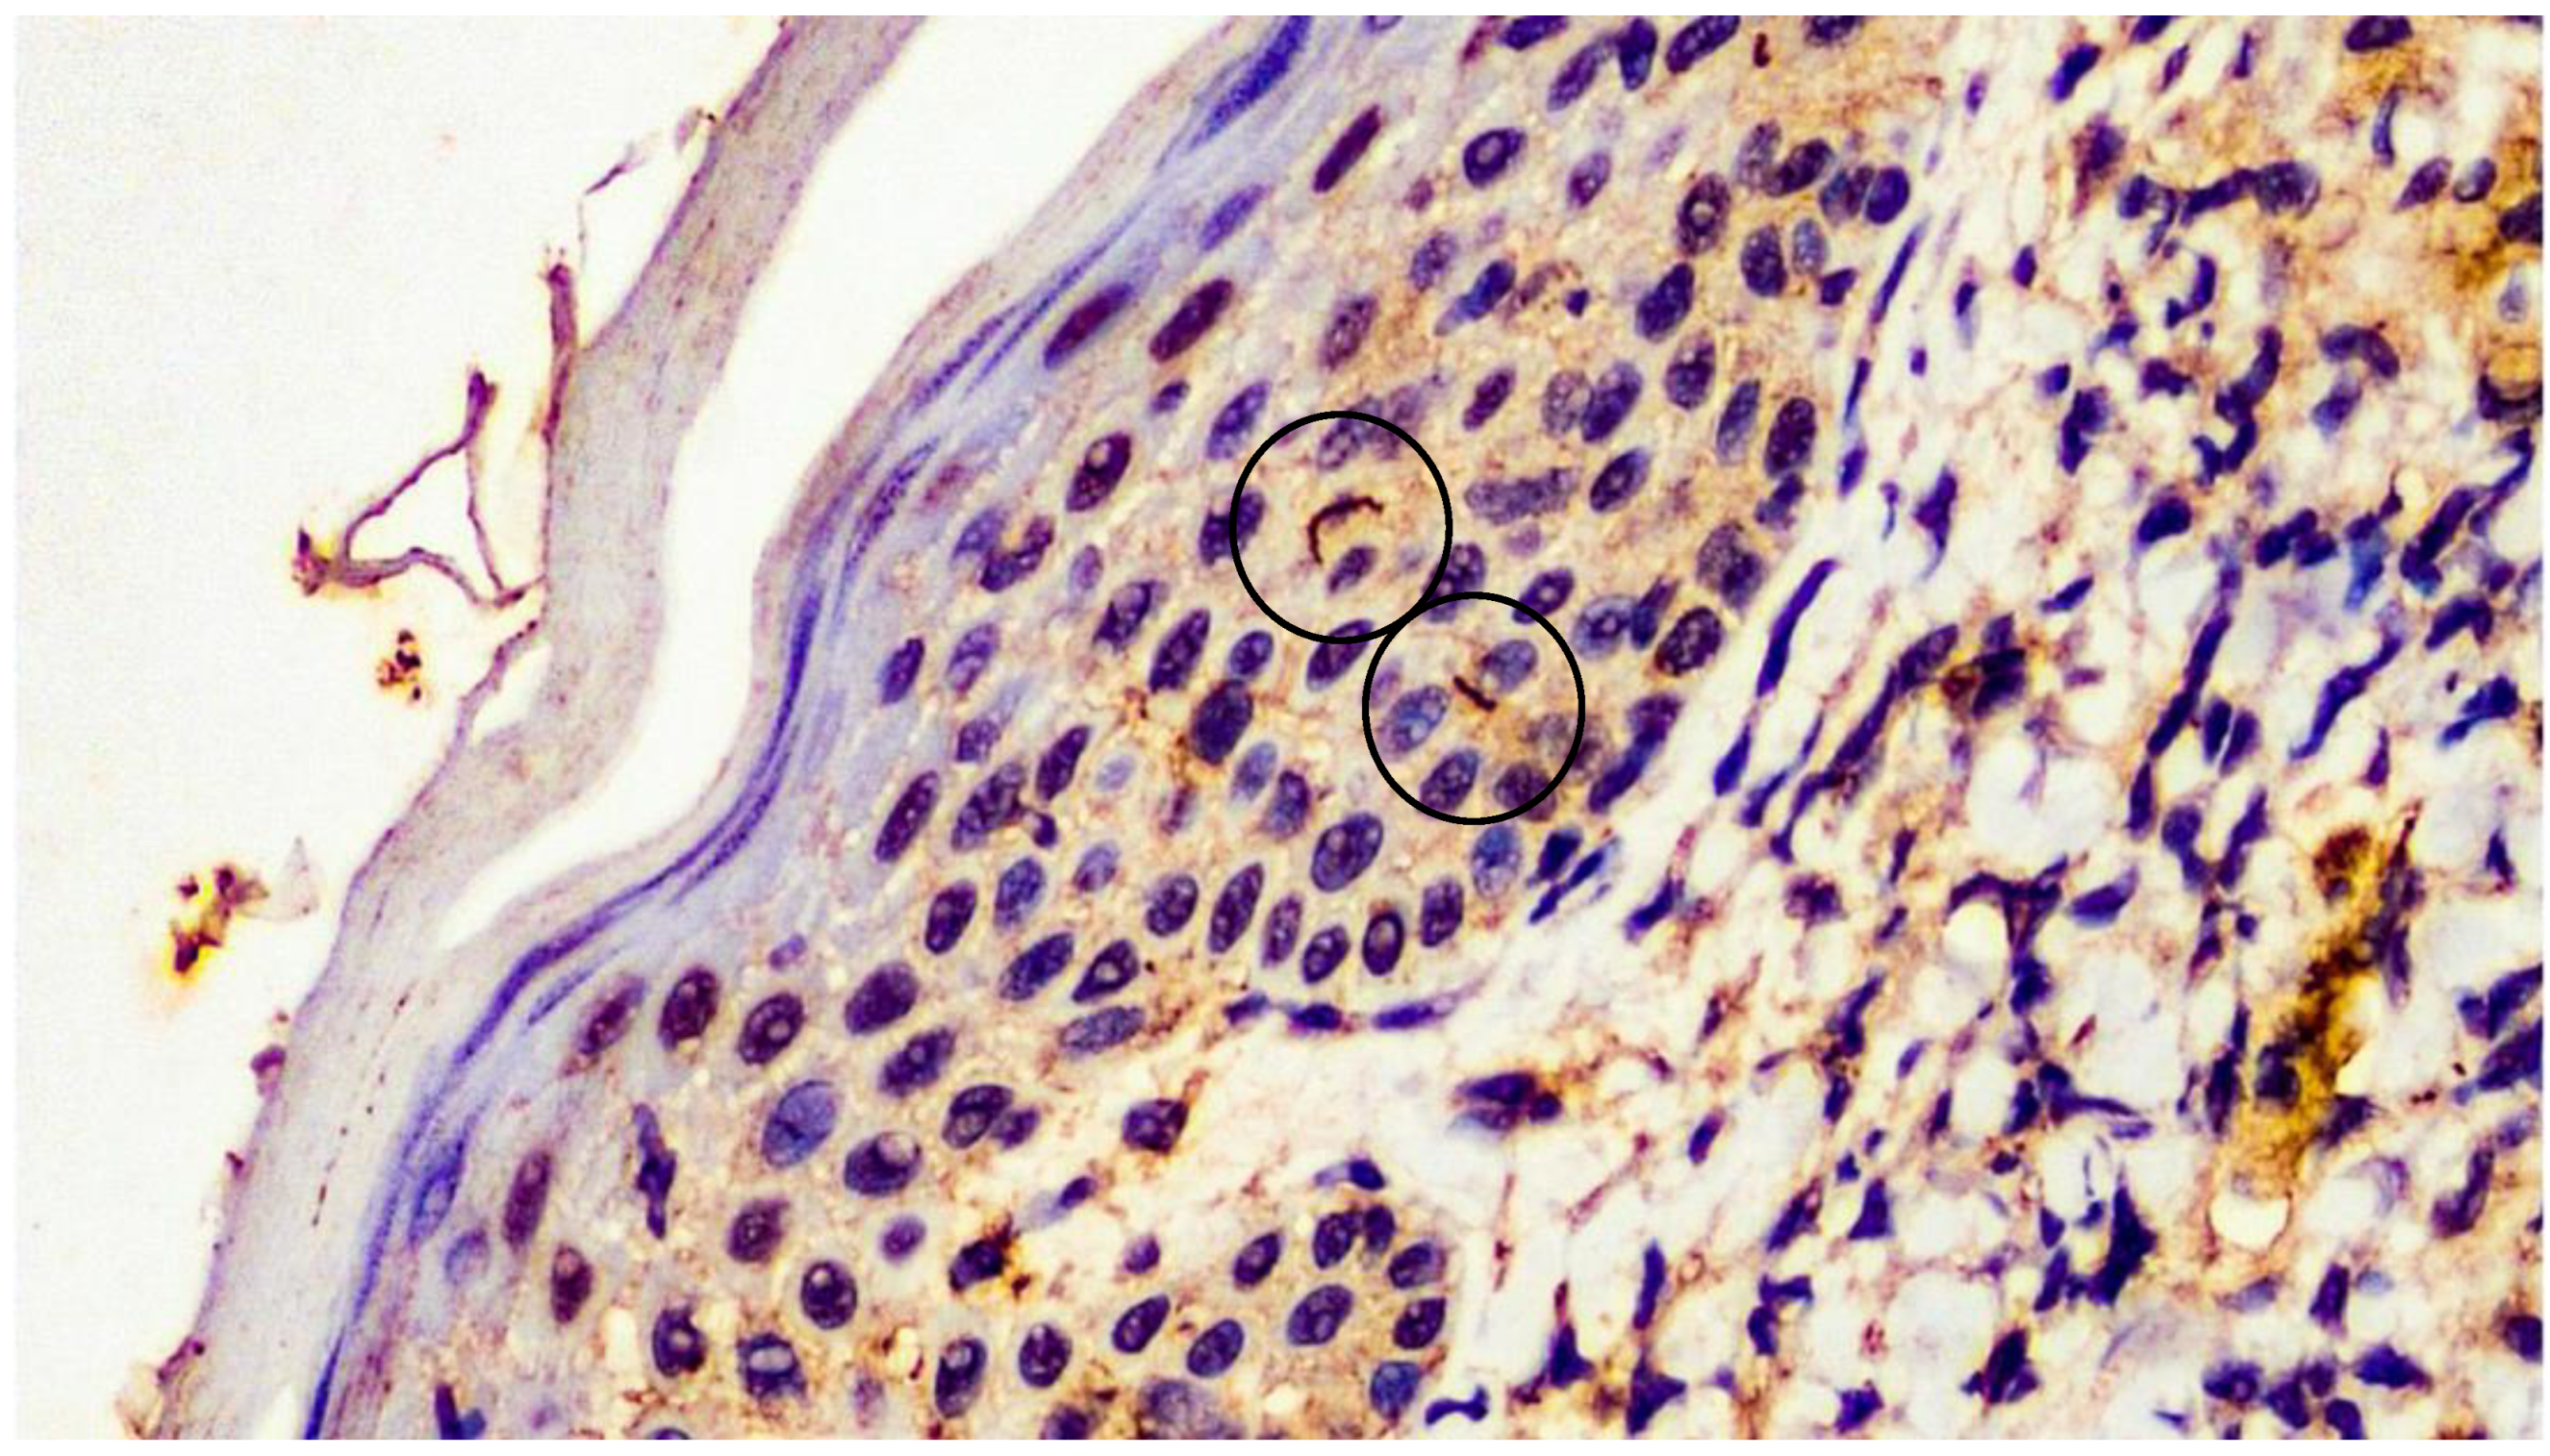

2. Case Presentation